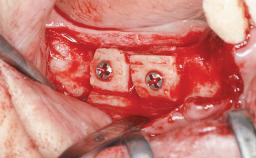

| Bone Augmentation | Horizontal|Sinus Floor Elevation|Staged|Vertical |

| Augmentation Materials | Autogenous chips|Autogenous block(s) |

| Bone Volume | Deficient vertically or deficient vertically AND horizontally |